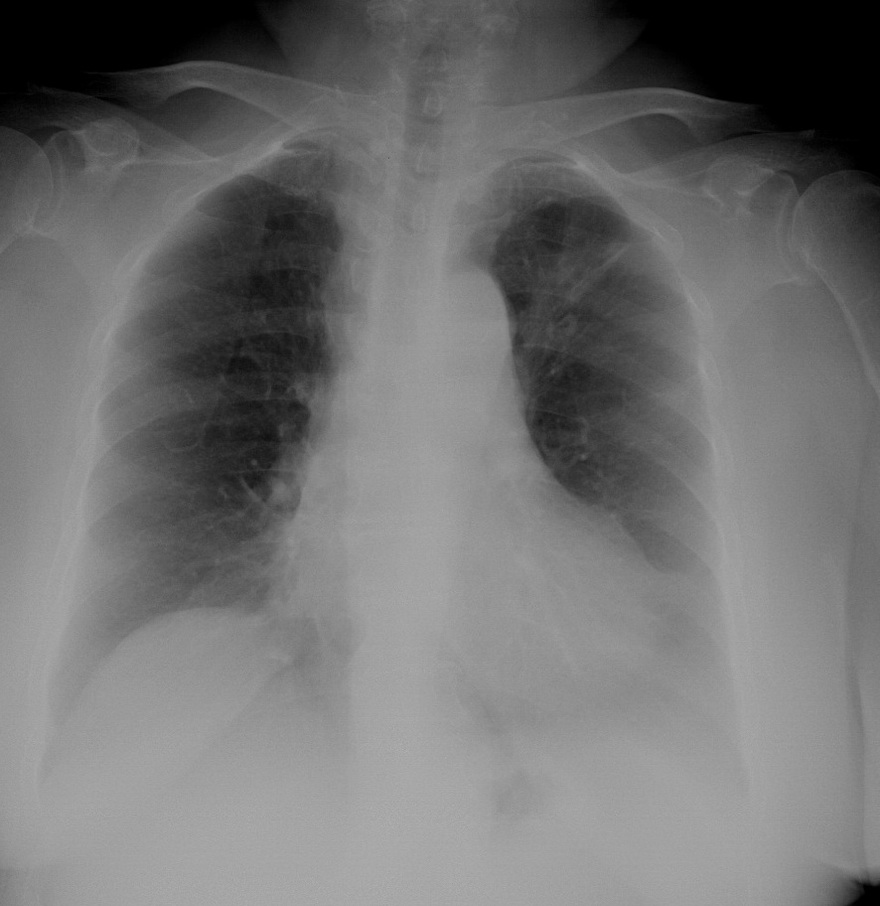

f,73y,住院体检,请问左肋膈角区透过度减低,左膈面显示不清能用心包脂肪垫解释吗?

我觉得像是胸膜粘连的影子,左侧肋膈角已消失!考虑胸膜粘连

心影增大,胸腔积液待排

胖人,心脏左位,考虑心包脂肪垫

心影增大,左肋膈角区透亮度减低,感觉没问题,不过还是小心为好,结合胸部透视。

左侧肋膈角区可用透视看看。左上阴影更值的关注

胖人,心脏左位,考虑心包脂肪垫 ,还有和乳房重叠,透视最好一起结合用

1:左上肺结核并左侧胸膜炎(积液并粘连).2:右膈下病变,建议b超检查.

左上肺陈旧性病变,余未见明显异常

单从本片来看,没有异常,左侧肋膈角只是模糊一点,但还是可见。此人可能较胖,左右乳房影有可能不对称。